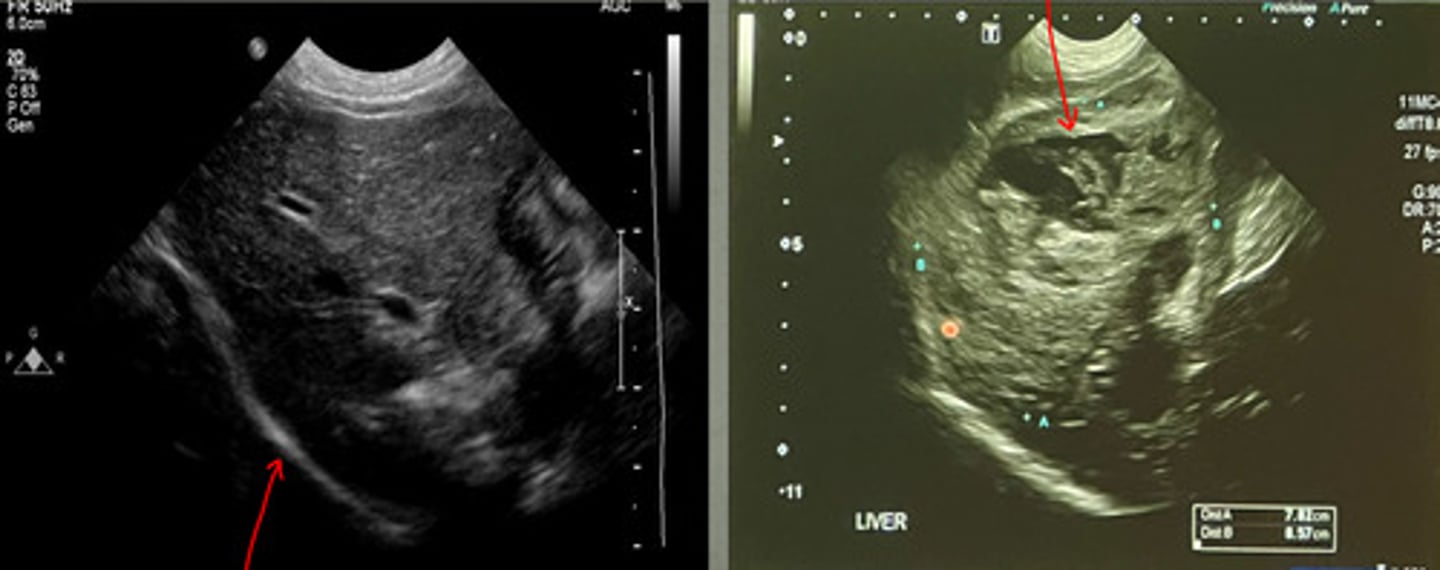

cranial border of liver

what part of the liver is this showing?

left caudal border of the liver

what part of the liver is this showing?

right caudal border of the liver

what part of the liver is this showing?

right- there is a mass on the ventral side

which of these US images of the liver is abnormal?

diaphragm

what is the red arrow pointing to in the left image?

which US image shows the normal liver?

focal mass

what focal change does this show in the liver?

nodular lesions

what is the red arrow indicating from this ultrasound of the liver?

abnormal

is this a normal or abnormal liver US?